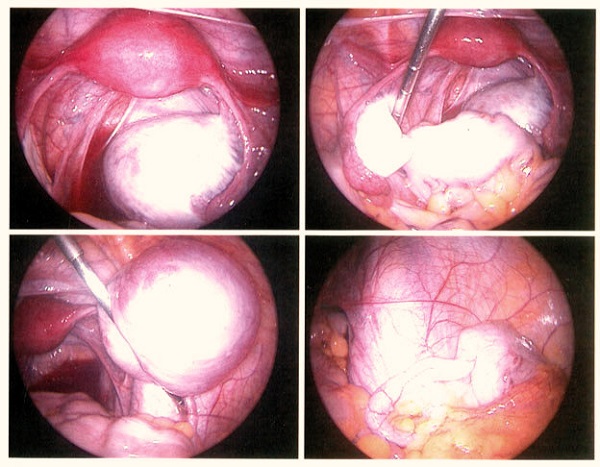

در صورتی که علائم شدید باشند، درمان های هورمونی موفق به تسکین بیمار نشوند و همچنین مشکلات بارداری ادامه یابد، جراحی تبدیل به انتخاب بعدی خواهد شد. طی عمل جراحی پزشک می تواند هر کدام از مناطق درگیر با آندومتریوز را مشخص کرده و اقدام به جداسازی ضایعات کند. معمولا بعد از جراحی و در حالتی که فرد قصد بارداری نداشته باشد، درمان های هورمونی مجددا شروع می شوند.